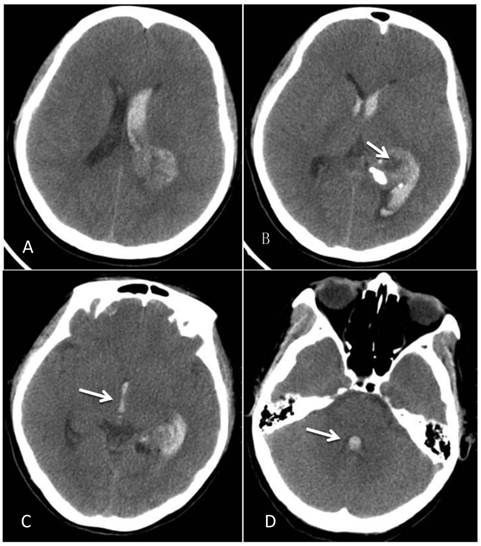

A 46-year-old female was admitted to the hospital due to a sudden onset of headache that had lasted for 5 hours. Physical examination showed neck stiffness and Kernig's sign but no other positive signs of the nervous system. Computed tomography (CT) showed a high-density space-occupying lesion in the trigone of the left lateral ventricle. Hemorrhage surrounded the lesion and formed a hematoma, which extended forward into the contralateral ventricle and affected the third and fourth ventricles (Figure 1). Computed tomography angiography (CTA) showed no intracranial artery malformation. The medial blood vessels of the lesion in the trigone of the lateral ventricle were disordered, and the lesion was supplied by anterior and posterior choroidal arteries. Maximum intensity projection clearly revealed a high-density calcification shadow at the rear of the lesion, and the surrounding brain tissues were mildly compressed (Figure 2). Magnetic resonance imaging (MRI) showed that the area of the lesion was 2.86 cm × 2.68 cm with mixed T1WI and T2WI signals. The lesion was heterogeneous in density, and its center was cystic. Slightly high abnormal T1WI and T2WI signals were noted in the bilateral lateral ventricles, and fluid was visible in the occipital horn of the left lateral ventricle (Figure 3).

Figure 2

CTA after the onset of intraventricular hemorrhage. A: No intracranial artery malformation was observed; medial blood vessels of the tumor in the trigone of the lateral ventricle were disordered, and the tumor was supplied by anterior and posterior choroidal arteries (oval area). B: Maximum intensity projection revealed a high-density shadow in the trigone of the left lateral ventricle; the surrounding vessels were disordered, and a high-density calcification shadow was detected at the rear of the lesion (arrow).